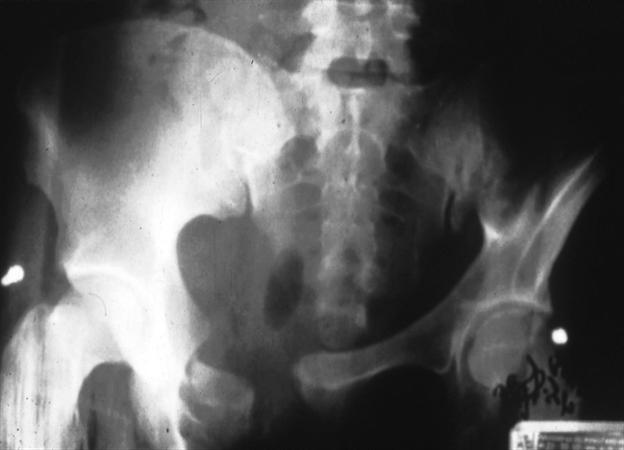

VS (vertical shear)는 hemipelvis 형태로 전이가 이뤄집니다. symphysis가 벌어지기도 하고 rami, iliac wing, sacral fx, SI jt posteriorly 모두 손상을 입게 됩니다.

천추골절을 따로 분류하기도 합니다. Denis classification

Sacral insufficiency fx 에서는 HONDA sign 이 보일 수 있습니다. (Hyundai sign으로 바꾸고 싶네요ㅎㅎㅎ)